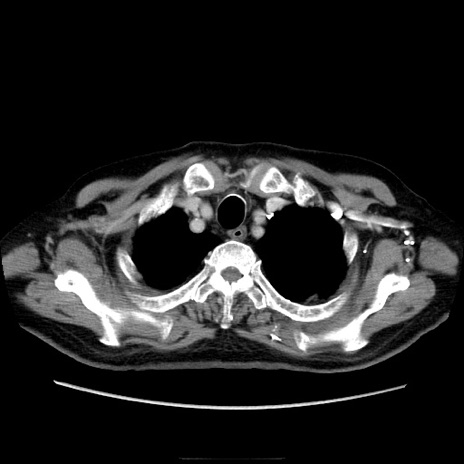

症例21(横断像)

【症例】70歳代男性

【主訴】腹痛

【現病歴】肝硬変・肝細胞癌にてかかりつけの方。約9時間前に食後より腹痛出現。症状が徐々に増悪し、嘔吐出現したため来院。

【既往歴】肝硬変、肝細胞癌(RFA、TACE後)

【身体所見】意識清明、表情苦悶様、BT 36℃、BP 129/78mmHg、P 88bpm、SpO2 97%(RA)、右上腹部から心窩部にかけて圧痛あり、反跳痛なし、筋性防御あり。

【データ】WBC 5800、CRP 0.16